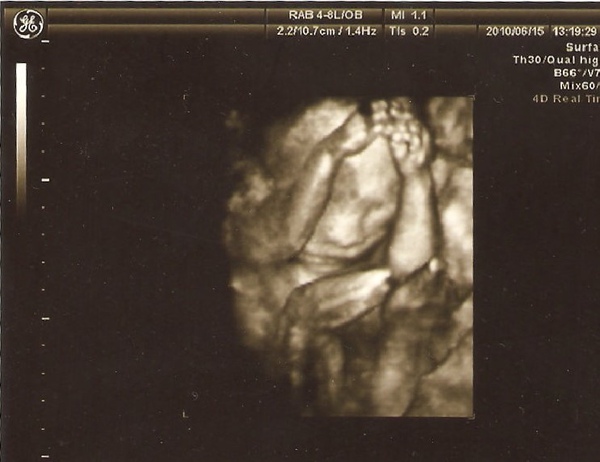

有時後切換4D畫面,讓我們比較清楚,畢竟2D不是每個畫面我們都能理解

過程中偶爾切換4D,後來醫生也說他很可愛(雖然是場面話,聽了還是很開心

4D照片雖然只能看外表,但是對我爸媽來說,這是他們可以理解的,看得很開心~

這是他們第一次看到不那麼像外星人的李小果,之前看起來都還很醜,今天看好多了!

這張照片同事說:一副苦惱的樣子 XD